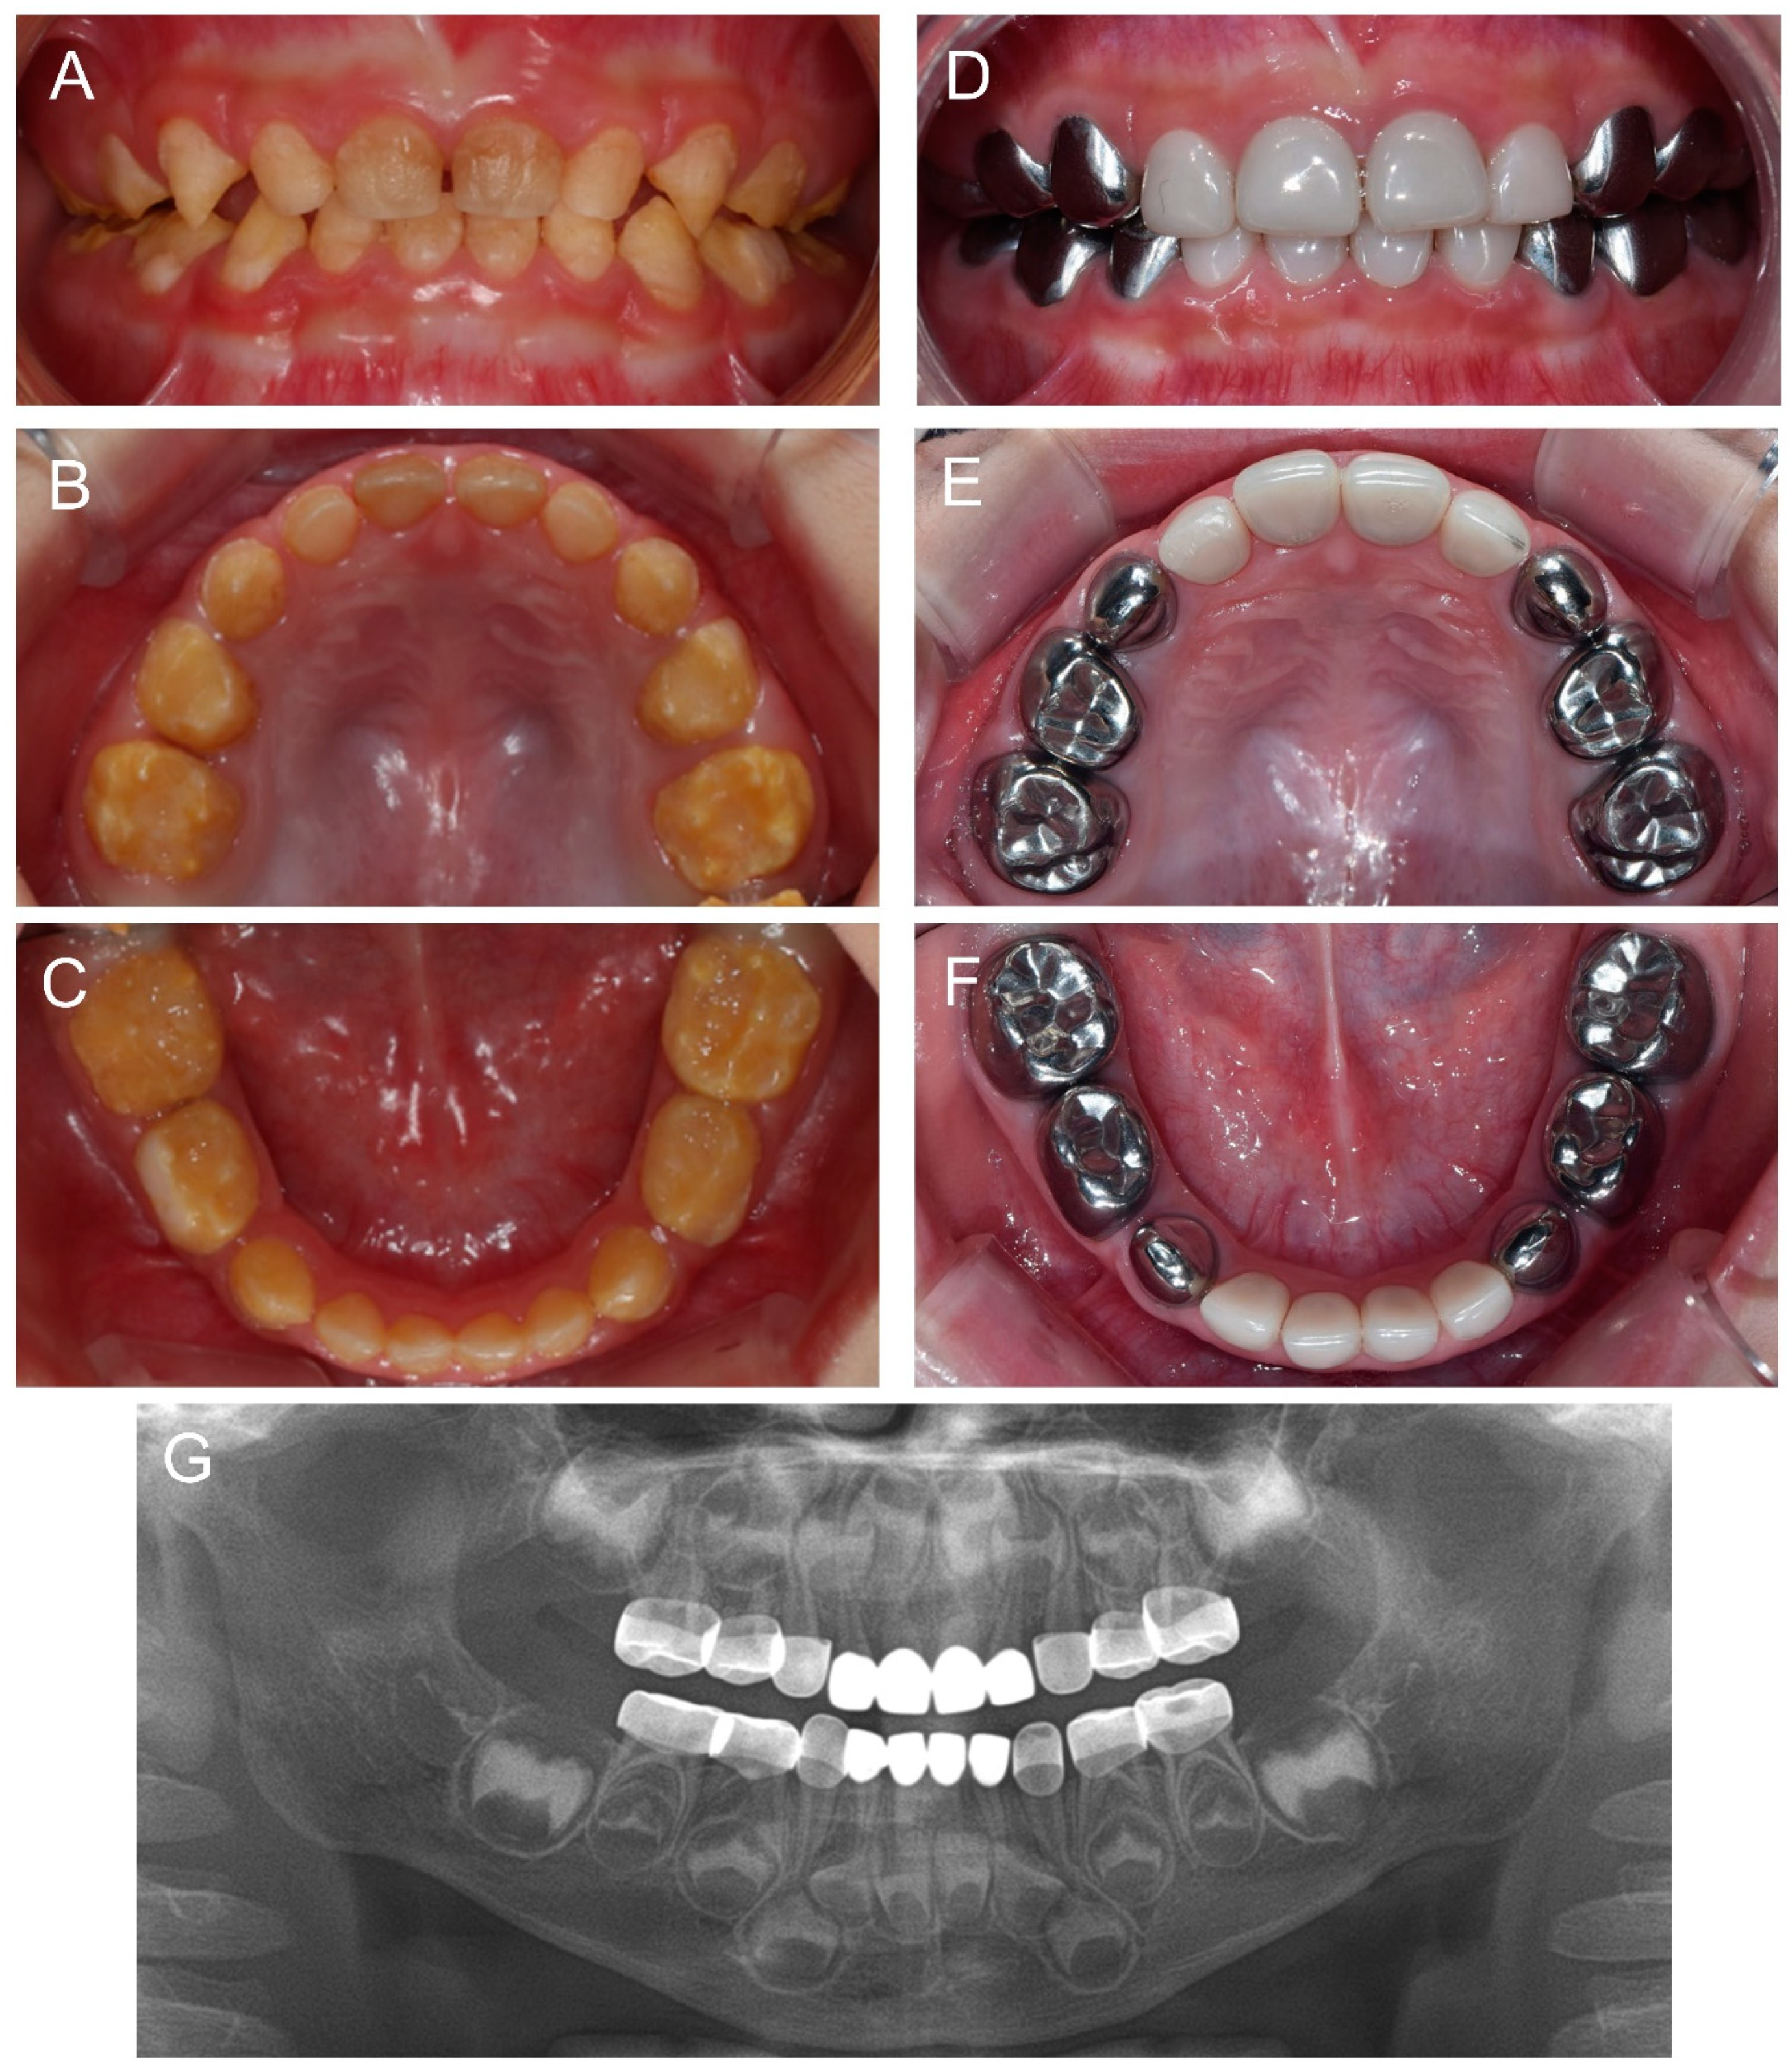

Another cousin (IV:2) of the proband, a younger brother of the affected individual (IV:1), presented for the same reason at age 1Y2M. The same treatment strategy was planned, and full-mouth restoration was performed at age 2Y9M. Deciduous molars and canines were treated with stainless steel crowns and all anterior teeth were treated with zirconia crowns (Figure 5).

Figure 5.

Clinical photos and panoramic radiograph of the affected individual (IV:2). (A–C) Clinical photos of the proband before the treatment at age 2 years 9 months. (D–F) Clinical photos of the proband after the treatment at age 3 years 6 months. The deciduous molars and canines were treated with stainless steel crowns and all anterior teeth were treated with zirconia crowns. (G) Panoramic radiograph at age 3 years 6 months.